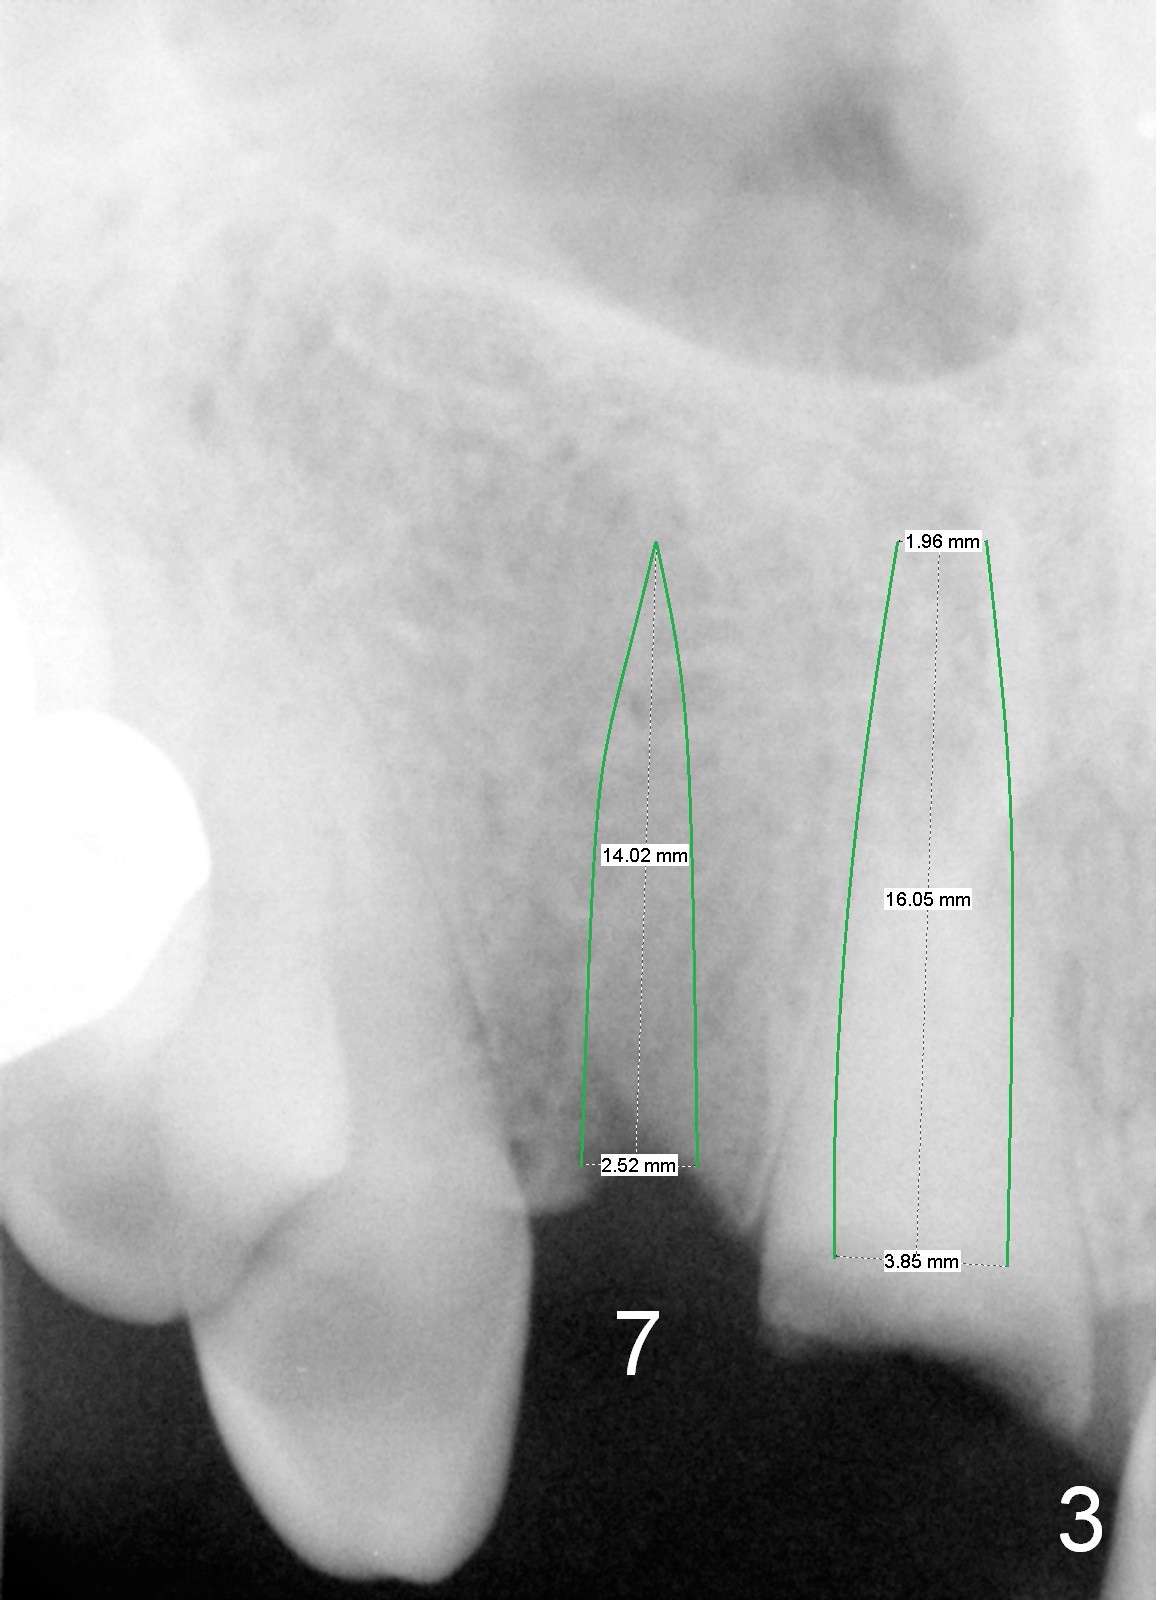

A 88-year-old man (CA) has severe xerostomia-induced caries. After caries control, implants will be placed at #7, 8 and 10 with narrow mesiodistal width (Fig.1,2). Note concavity at the apical buccal plate (*). To prevent perforation, an angled 1-piece implant will be used at #7. Try to place the implant in the middle of the alveolus (digital palpation while drilling) and let the angled abutment take care of the trajectory. To preserve papillae, flapless approach is going to be adopted. Initial depth at these sites will be 12,14 and 14 mm, respectively (Fig.3,4). Use Boley gauge to measure widths of the root to determine the diameter of the implant.